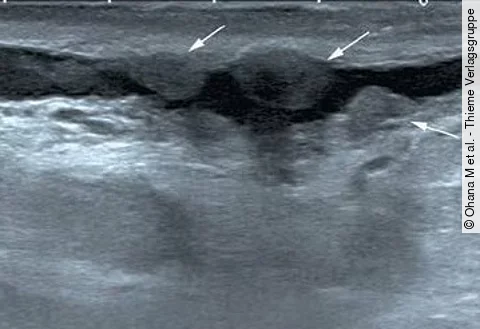

Die 59-jährige Patientin gibt an, zunehmende Atembeschwerden zu haben. Sie weiß von einer Asthma-Erkrankung, die seit vielen Jahren therapiert wird, und ist Nichtraucherin.